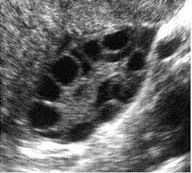

وی افزود: گاهی تعداد زیادی از فولیکولها با هم شروع به رشد میکنند و به مرحله تخمک میرسند که موجب بروز عارضه تخمدان پلیکیستیک میشود.

وی افزود: همچنین گاهی در سونوگرافی زنان سالم که سیکل طبیعی دارند ممکن است کیستهایی به اندازه 20 تا 30 میلیمتر دیده شود که جای نگرانی نبوده و اقدامی نیز برای این کیستها نیاز نیست اما کیستهای بزرگتر از 3 میلیمتر نیاز به بررسی بیشتری دارند هر چند که کیستهای 30 تا 70 میلیمتر نیز نیاز به جراحی ندارند و با درمان سرپایی قابل برطرف شدن هستند.